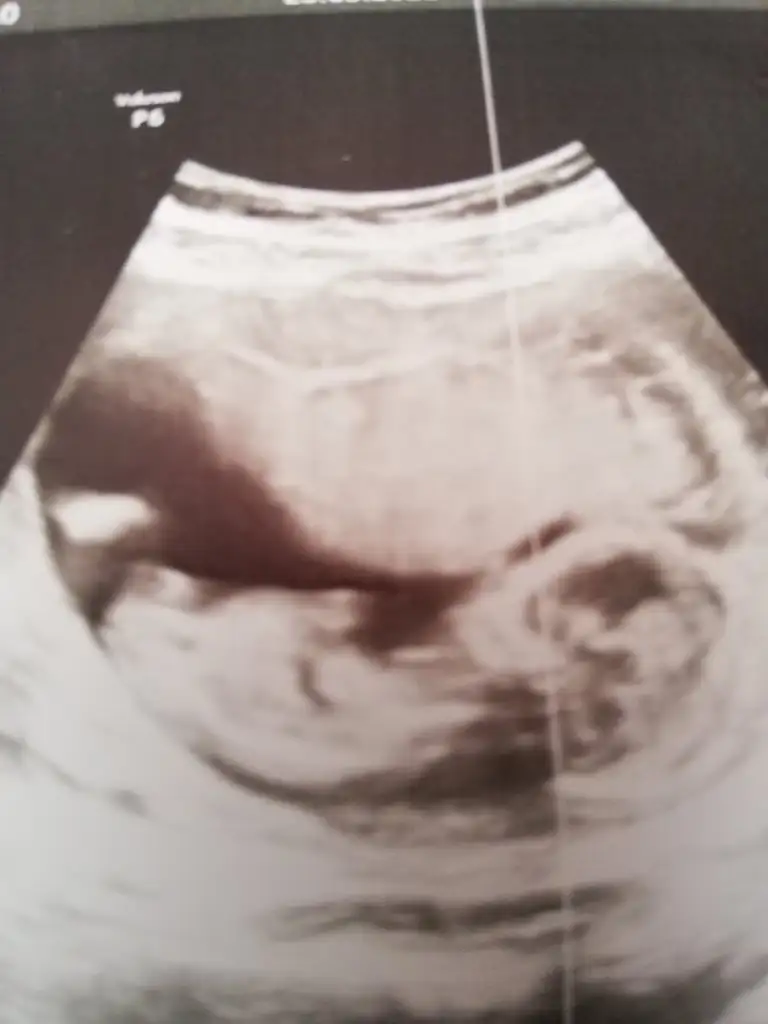

Merhaba Ikra meyra Ikra meyra 11+4te usgmize erkek gibi demiştin. Bugün kontrole gittik bebeğimiz hep poposunu döndü :) bacak arasında da kordon varmış doktor bir türlü emin olup birşey söylemedi. Usg ekliyorum pek nubu görünmüyor gibi ama belki sen görebilirsin :) sonunucu baş aşağı olduğu için onu ters çevirip ekledim. Sana bir fikir veriyor mu acaba 😌

Emin olamadım bundan canım tıp kıza benzettim 🙈

Canım Ikra meyra Ikra meyra bu arada sen kız dedikten sonra iyice inceledim ve 3 çizgi gördüm 🤗 aşağıda işaretledim. Yalnız internette bakarken erkek 3 çizgisinde bizimki gibi birinin ayrık gibi olduğunu gördüm. Sence son kararın ne 😌 kız mı erkek mi? Söz bir daha rahatsız etmeyeceğim seni 🤗

Senin bebek kız görünüyor tipide kız gibi